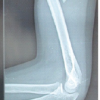

An 11-year-old, right-hand dominant boy presented in casualty with history of fall from window on his left hand1 day back with pain, swelling and deformity in the left forearm with bleeding from left forearm which was dressed at local hospital and loss of movement of thumb and fingers of left hand. On examination, there was a wound of size 1 cm on mid-forearm over the ulnar aspect (Fig.1). Extension of fingers at metacarpophalangeal joints and thumb was lost with intact sensations suggestive of posterior interosseus nerve involvement. Wrist movements could not be assessed due to pain in the wrist. No vascular was deficit was present. X-rays were performed which suggested type two epiphyseal separation of the proximal radius with fracture shaft of the ulna with lateral angulation (Fig.2). Radiocapitellar joint congruity was maintained in the views performed. X-rays of wrist suggested fracture both bones distal forearm, with Salter-Harris Type 2epiphyseal injury in distal radius and fracture of distal shaft of ulna (Fig.3). Intravenous antibiotics were started, and splintage was given, and the patient kept for surgery the following morning.